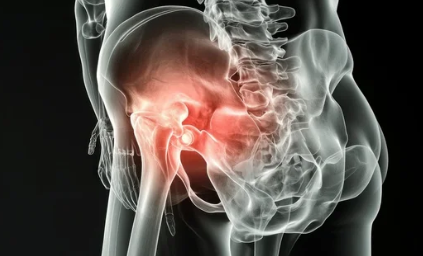

3. 노인 고관절 탈구의 증상

고관절이 탈구되면 즉각적인 통증과 보행 장애가 발생합니다.

✅ 주요 증상

- 엉덩이 및 사타구니 부위 극심한 통증 (움직일 때 심해짐)

- 다리의 길이 차이 발생 (탈구된 쪽이 짧아짐)

- 다리 모양의 비정상적인 변형 (내회전 또는 외회전)

- 일어서거나 걸을 수 없음

- 탈구된 부위의 부종 및 멍

- 신경 압박 시 발가락 또는 다리 감각 저하